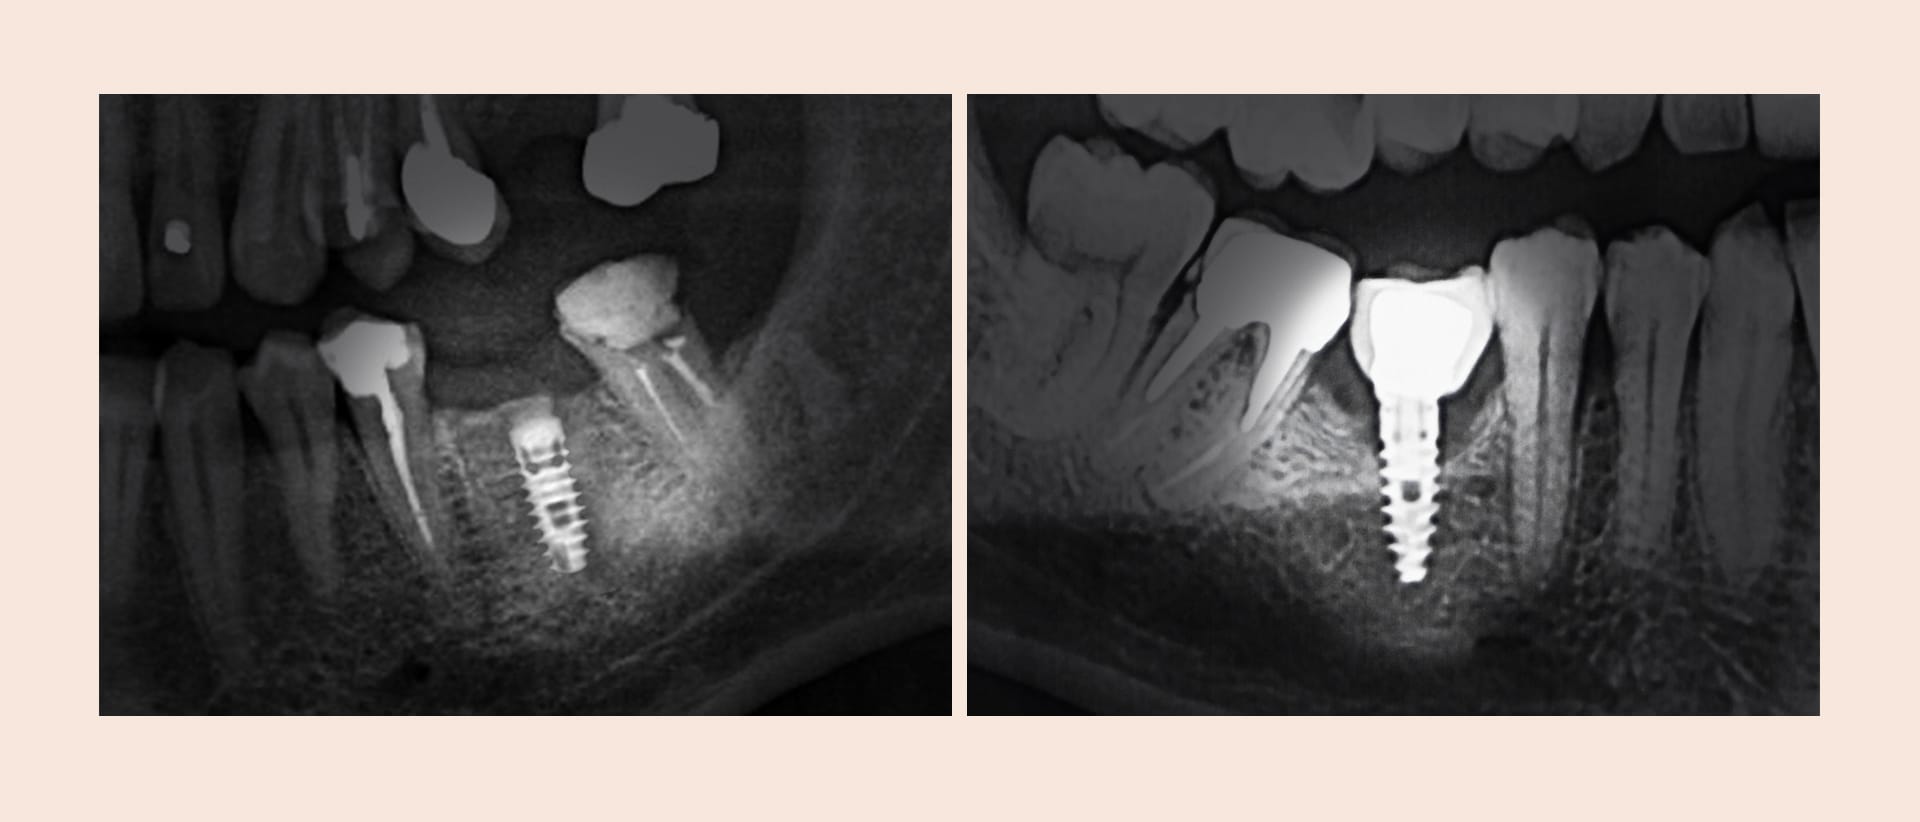

- X-ray에서 임플란트 주변 뼈 손실이 확인됩니다

- 임플란트 뿌리가 많이 드러나서 지속적으로 골소실이 일어나요

| 정밀 진단 | 3D CT 등 디지털 장비로 임플란트 손상 정도, 뼈 흡수 범위, 염증 확산 부위를 세밀하게 분석합니다. |